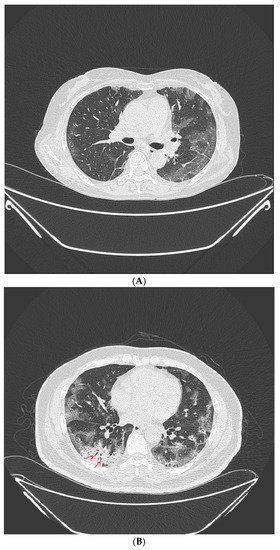

LDCT were obtained on symptomatic patients at high risk of screening with a 64-section scanner (Brilliance CT, Philips Healthcare) [16]. One radiologist (over 15 years of experience) and one pulmonology specialist (over 8 years of experience) retrospectively reviewed all LDCT images. Lobar distribution was assessed by observing the number of involved lobes, laterality, cephalocaudal distribution, and axial distribution [17]. In terms of pattern, ground glass opacity (GGO), consolidation, and crazy-paving pattern was assessed according to the definitions based on the Fleischner Society Nomenclature Committee recommendations [17,18]. (Figure 2A–C) Observation of the following characteristics was considered a typical finding for COVID-19; (1) peripheral, bilateral, GGO with or without consolidation or visible intralobular lines (“crazy-paving”), (2) Multifocal GGO of rounded morphology with or without consolidation or visible intralobular lines (“crazy-paving”), (3) Reverse halo sign or other findings of organizing pneumonia [18].

Figure 2.

Typical findings for COVID-19 on CT scans. (A) Ground-glass opacity shows as a modest increase in lung attenuation on lung window CT images, not obscuring the pulmonary vessels. (B) Consolidation appears as high-density patchy opacities that obscure the margins of vessels and airway walls, inside which air bronchogram (arrow) could be observed. (C) Crazy-paving pattern appears as thickened interlobular septa and intralobular lines superimposed on a background of ground-glass opacity.